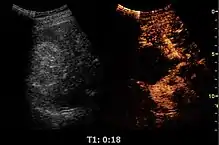

Contrast-enhanced ultrasound (CEUS) is the application of ultrasound contrast medium to traditional medical sonography. Ultrasound contrast agents rely on the different ways in which sound waves are reflected from interfaces between substances. This may be the surface of a small air bubble or a more complex structure. Commercially available contrast media are gas-filled microbubbles that are administered intravenously to the systemic circulation. Microbubbles have a high degree of echogenicity (the ability of an object to reflect ultrasound waves). There is a great difference in echogenicity between the gas in the microbubbles and the soft tissue surroundings of the body. Thus, ultrasonic imaging using microbubble contrast agents enhances the ultrasound backscatter, (reflection) of the ultrasound waves, to produce a sonogram with increased contrast due to the high echogenicity difference. Contrast-enhanced ultrasound can be used to image blood perfusion in organs, measure blood flow rate in the heart and other organs, and for other applications.

Untargeted CEUS

Untargeted microbubbles, such as the aforementioned SonoVue, Optison, or Levovist, are injected intravenously into the systemic circulation in a small bolus. The microbubbles will remain in the systemic circulation for a certain period of time. During that time, ultrasound waves are directed on the area of interest. When microbubbles in the blood flow past the imaging window, the microbubbles' compressible gas cores oscillate in response to the high frequency sonic energy field, as described in the ultrasound article. The microbubbles reflect a unique echo that stands in stark contrast to the surrounding tissue due to the orders of magnitude mismatch between microbubble and tissue echogenicity. The ultrasound system converts the strong echogenicity into a contrast-enhanced image of the area of interest. In this way, the bloodstream's echo is enhanced, thus allowing the clinician to distinguish blood from surrounding tissues.